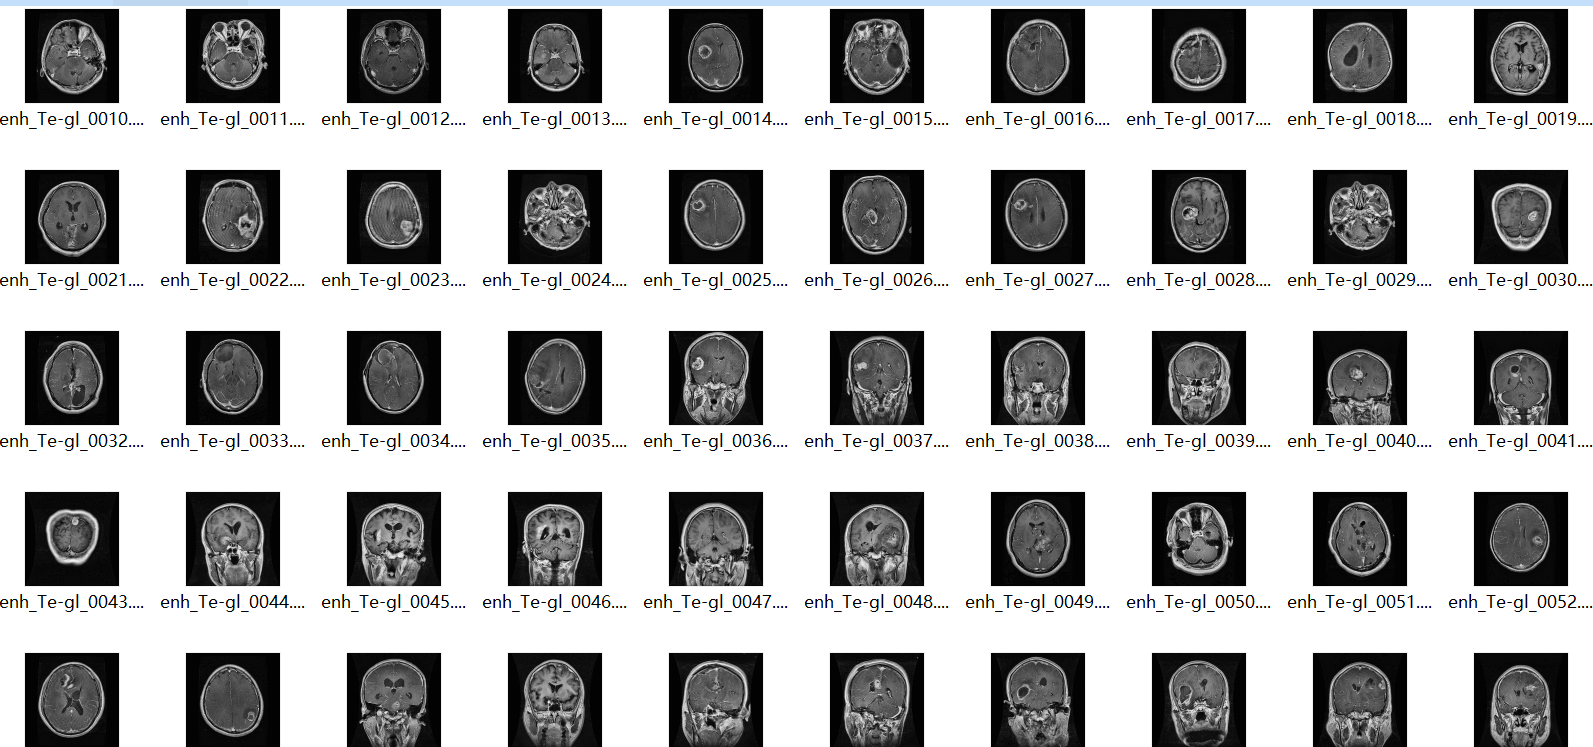

脑肿瘤MRI分割与分类数据集(5000张切片+2700例分割掩码)| 含无肿瘤/神经胶质瘤/脑膜瘤/垂体瘤数据(附获取途径+兼容格式)

该数据集聚焦脑肿瘤医学影像研究,专为脑肿瘤分割(肿瘤区域精准定位) 与分类(肿瘤类型识别) 双任务设计,可直接用于AI辅助诊断模型训练(如CNN、Transformer等算法)、临床影像分析方法验证,解决当前脑肿瘤研究中“样本量不足、标注不完整”的痛点,适配全球医学研究机构、高校医学院、医疗AI企业的研发需求,数据均经过隐私脱敏处理,符合医学伦理规范。

二、数据核心信息:数量与分类

1. 总规模:约5000张脑肿瘤MRI切片,覆盖“无肿瘤+3类常见脑肿瘤”场景,样本分布均衡,避免模型偏倚;

2. 肿瘤类型细分:

无肿瘤(No Tumor):约1200例,为正常脑MRI切片,用于模型对照训练;

神经胶质瘤(Glioma):约1300例,含低级别、高级别胶质瘤亚型,覆盖不同病灶大小;

脑膜瘤(Meningioma):约1250例,包含颅内不同位置(如大脑凸面、颅底)病灶;

垂体瘤(Pituitary):约1250例,含增强扫描序列切片,适配垂体瘤特异性诊断需求;

3. 分割掩码数据:约2700例,精准标注肿瘤核心区、水肿区(部分类型)等关键区域,标注由资深放射科医师审核,确保准确性。

五、数据集目录(按类型分类)

1. 基础MRI切片数据集(共约5000张)

1.1 无肿瘤(No Tumor)子目录:1200张正常脑MRI切片(含T1、T2加权序列);

1.2 神经胶质瘤(Glioma)子目录:1300张切片(分低级别、高级别子文件夹);

1.3 脑膜瘤(Meningioma)子目录:1250张切片(按病灶位置分类);

1.4 垂体瘤(Pituitary)子目录:1250张切片(含增强扫描序列子文件夹);

2. 分割掩码数据集(共约2700例)

2.1 神经胶质瘤分割掩码:700例(标注肿瘤核心区、水肿区、增强区);

2.2 脑膜瘤分割掩码:650例(标注肿瘤实质区);

2.3 垂体瘤分割掩码:650例(标注垂体瘤及周围结构);

2.4 无肿瘤对照掩码:700例(标注正常脑组织结构);